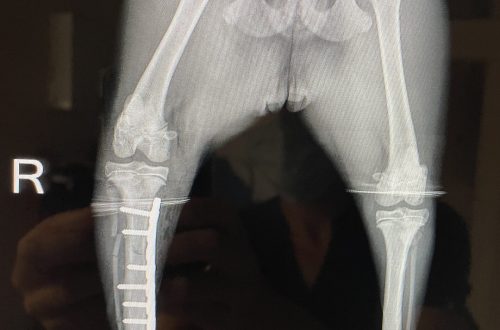

Musculoskeletal

Achilles Tendon Injury is an injury to any of the tendons that attach to the calcaneus bone. The tendons that make up the achilles mechanism include the gastrocnemius tendon, common tendon of the biceps femoris, and the superficial digital flexor tendon.